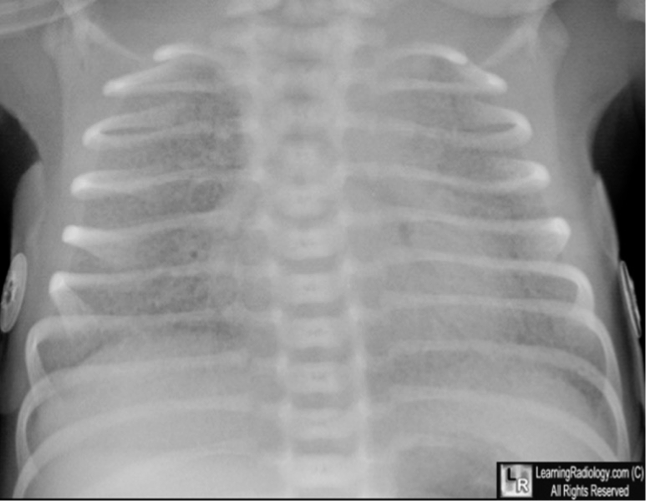

Preterm 29-weeks gestation C/S delivery showed severe respiratory distress soon after birth. This chest x-

ray was taken at age of 6 hours.

Q1: ground glass appearance, wide intercostal space.

Q2: Neonatal respiratory distress syndrome.

Q3: mechanical ventilation, give Surfactant for lungs maturation.

Xray findings

- White lung

- Air bronchogram

- Ground glass appearance

- low lung volume

What is your diagnosis? RDS

What is the definite treatment? Surfactant.